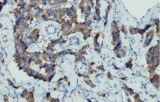

Primary antibodies for immunohistochemistry (IHC) with CE/IVD marking are essential reagents in diagnostic and research pathology, enabling the specific detection of target antigens in formalin-fixed paraffin-embedded (FFPE) tissue sections.

- In gastrointestinal stromal tumors (GISTs), KIT (CD117) expression is reliably detected by IHC, while PDGFRA mutations are evaluated through molecular testing, aiding in targeted therapy decisions.

Beyond diagnostic classification, IHC contributes to prognostic assessment and guides personalized therapeutic strategies in GI oncology.